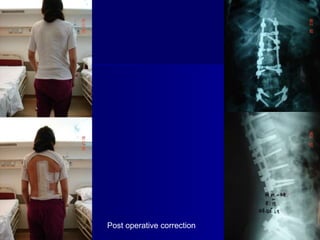

Double Spinal Deformity: a) Idiopathic

adolescent scoliosis

b) Spondylolysis - spondylolisthesis

Post operative correction